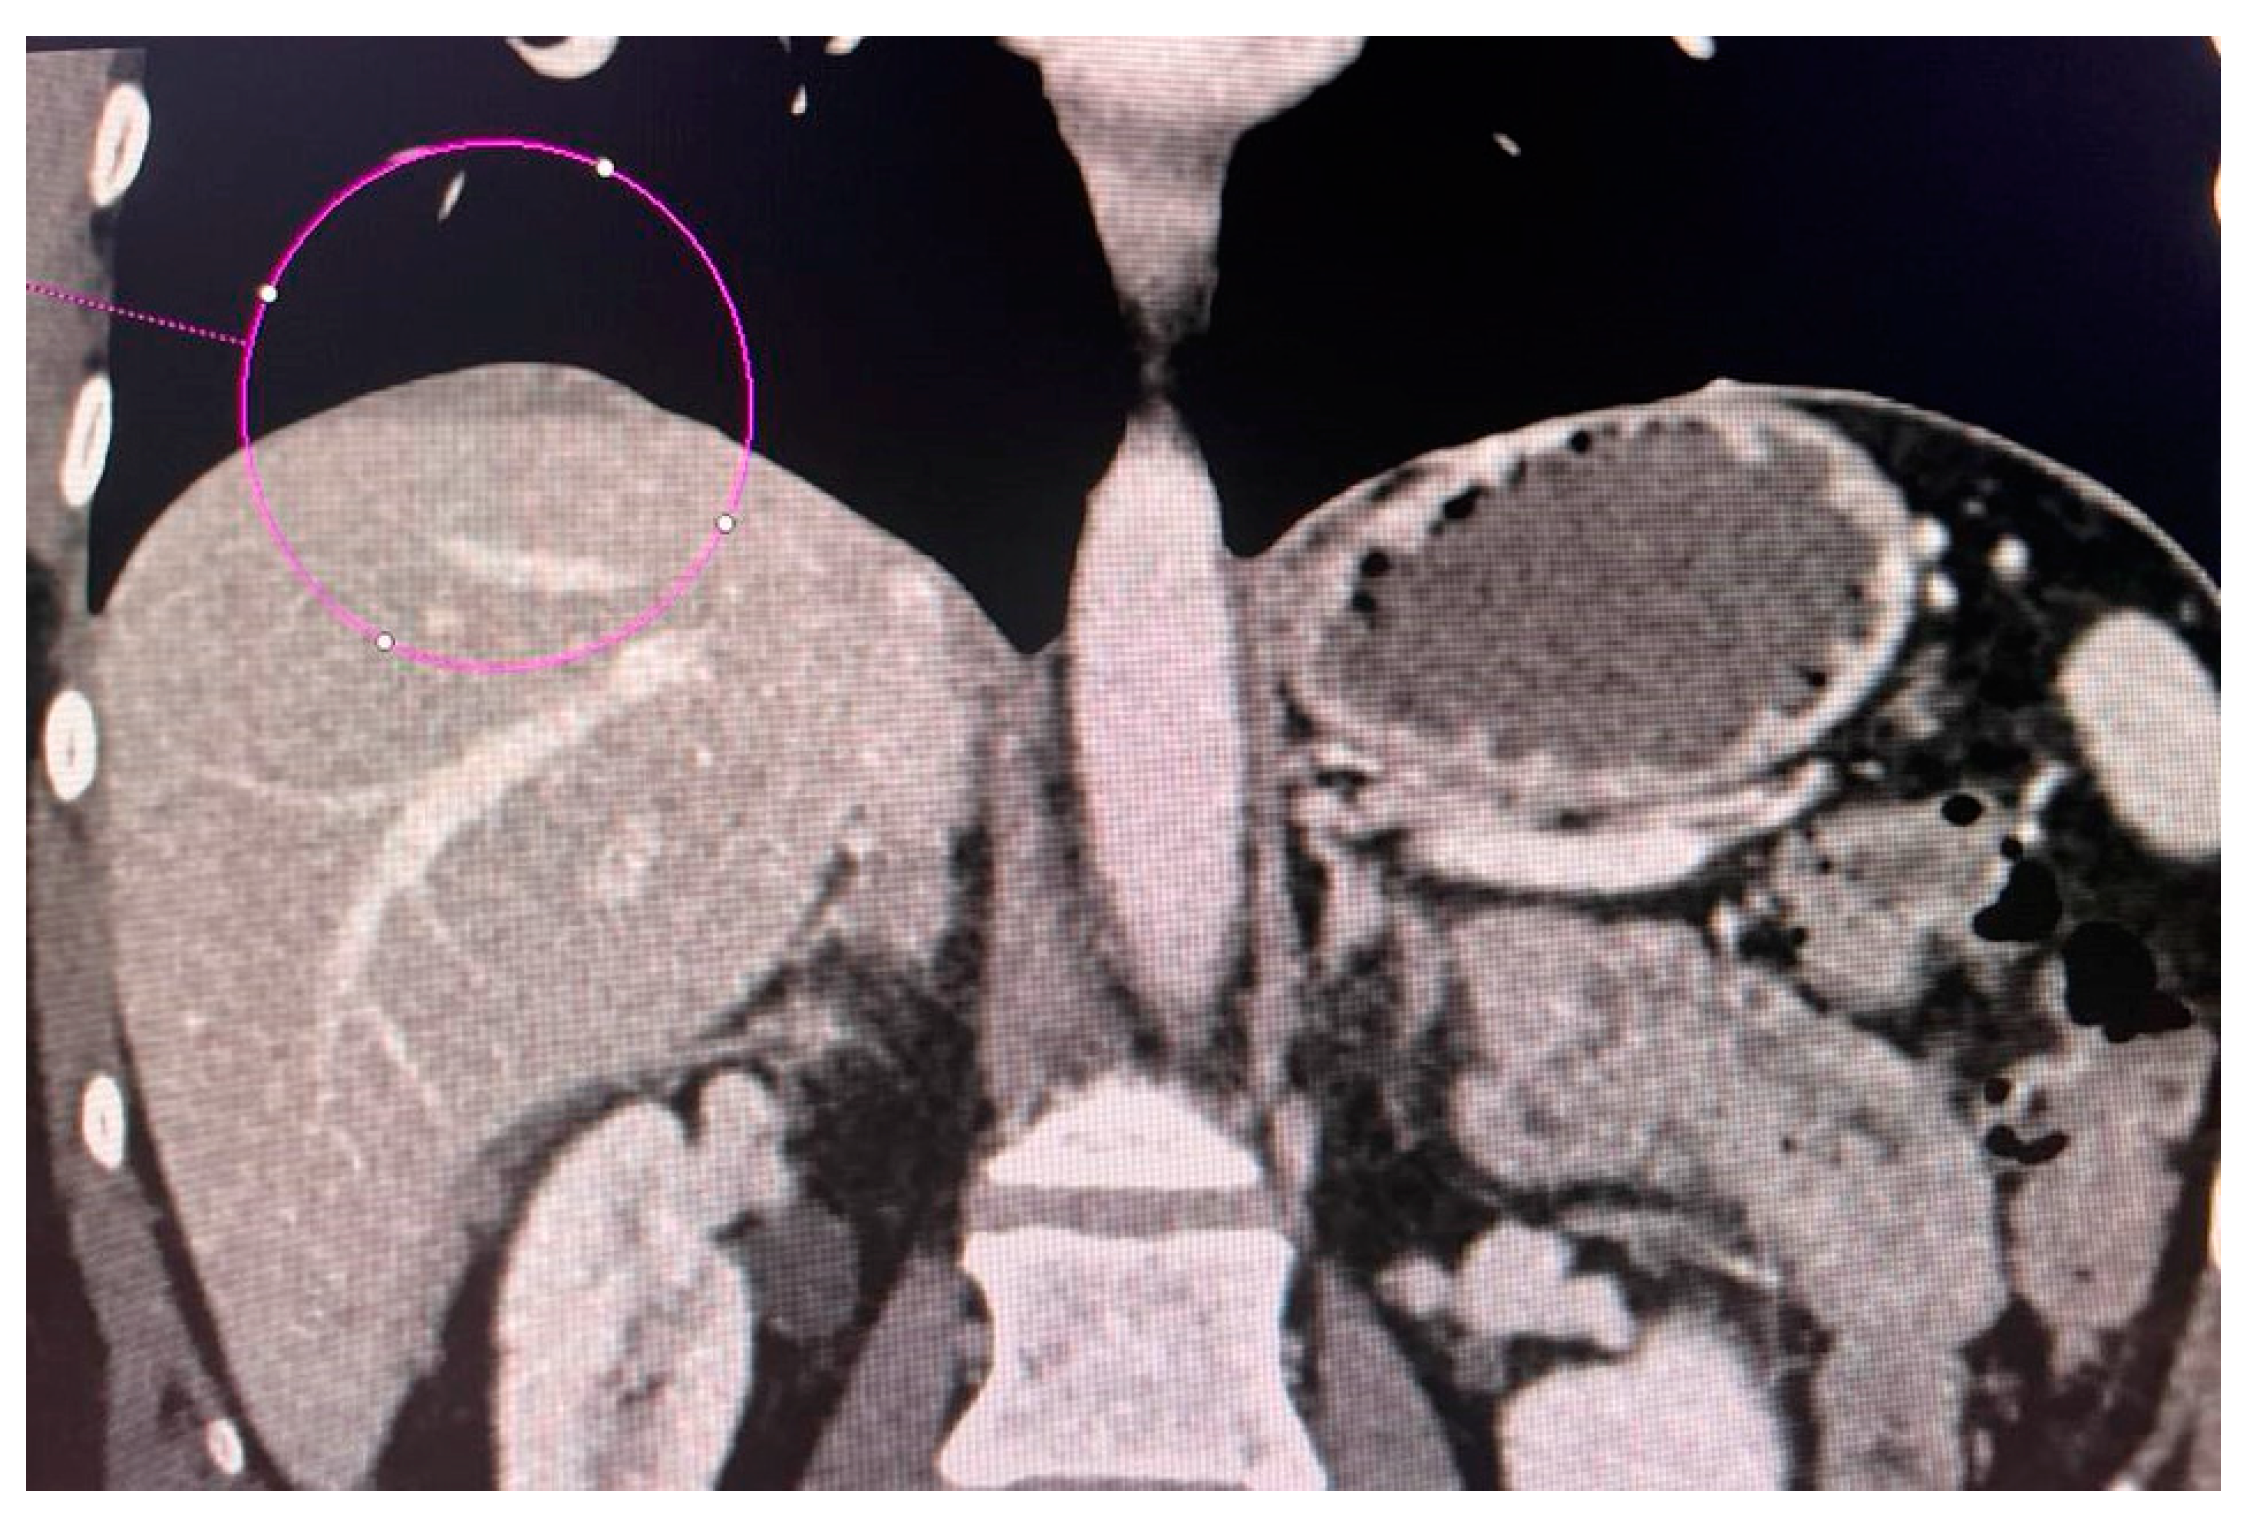

2.3. Computed Tomography Examination